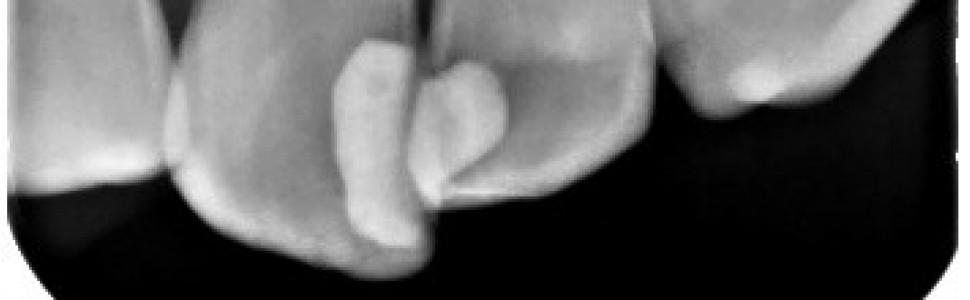

Resorpcja jest jedną z chorób prowadzących do utraty twardych tkanek zęba. Etiopatogeneza nie została do końca poznana. Leczenie resorpcji polega na zatrzymaniu procesu resorpcyjnego i odtworzeniu utraconych struktur zęba. W pracy przedstawiono rezultaty leczenia resorpcji wewnętrznej w zębie 22 z wykorzystaniem cementu krzemianowo-wapniowego, MTA (mineral trioxide aggregate).

Resorption is one of the diseases leading to the loss of dental hard tissues. Etiopathogenesis is not fully understood. The treatment involves stopping the process and restoring lost tooth structures. The paper presents the results of the treatment of internal resorption in tooth 22 with the use of calcium silicate cement, MTA (mineral trioxide aggregate).